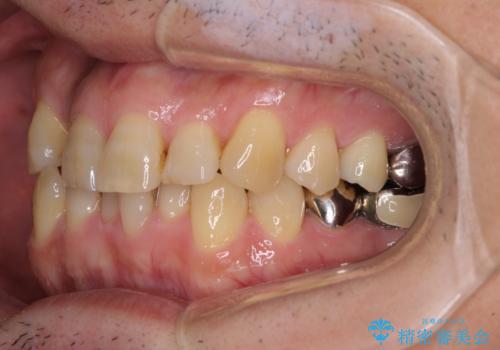

- 近医にてブリッジ治療を行った歯が痛くてたまらないとのことで来院された患者様です。

診察を行ったところ、奥の土台になっている歯は神経組織が失活しており、根尖部に病変があり、そこが原因で痛みを生じている状態でした。

根管治療を行うためにブリッジを除去したところ、むし歯が歯肉の奥深くにあまで及んでいたため、歯周外科処置によりむし歯が歯肉縁より浅い位置へと改善することとしました。

ここまでの治療を提案したところで、折角なのでしっかり治療を行いたいとのことで、前歯のデコボコやクロスバイトを改善するための矯正治療を行うこととしました。